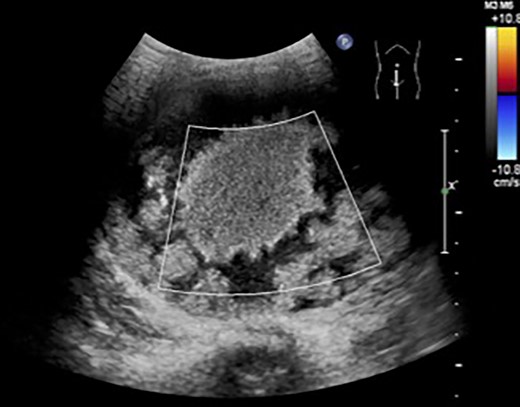

The patient was a 10-year-old girl. She visited our hospital after her grandmother noticed a mass in her lower abdomen that she had been aware of for 6 months. Abdominal ultrasonography revealed that she had a large mass centered in her lower abdomen. The tumor border was clear, the internal structure was heterogeneous and the blood flow was poor (Fig. 1). We suspected an ovarian tumor, but blood tests showed no elevated tumor markers such as AFP and CA19–9. Abdominal magnetic resonance imaging revealed a cystic mass 10 cm in diameter with high intensity on T1-weighted images and high intensity on T2-weighted images (Fig. 2). Abdominal computed tomography revealed a spleen near the navel and a cystic lesion with poor contrast that continued from the lower pole of the spleen (Fig. 3).

Abdominal ultrasonography revealed a large mass centered in her lower abdomen. The tumor border was clear, the internal structure was heterogeneous and the blood flow was poor.